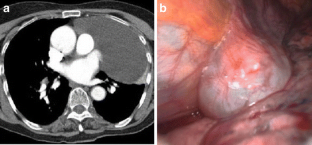

Fig. 1